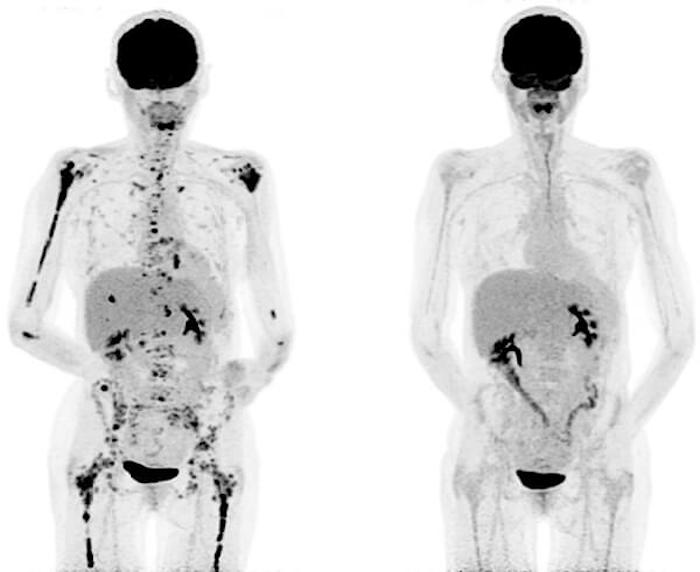

CART T-cell therapy eradicates tumors in nearly all patients with chronic lymphocytic leukemia (CLL) who had exhausted other treatment options, researchers at the Fred Hutchinson Cancer Research Center have reported.

It wasn’t until the second patient, Doug Olson, who received his CAR T cells about six weeks after Ludwig, that Porter had a eureka moment. When he received the call that Olson was also running a high fever, having trouble breathing and showing abnormal lab results, Porter realized that these were signs that the treatment was working. “It happens when you kill huge amounts of cancer cells all at the same time,” Porter says. What threw him off initially is that it’s rare for anything to wipe out that much cancer in people with Ludwig’s and Olson’s disease. June and Porter have since calculated that the T cells obliterated anywhere from 2.5 lb. to 7 lb. of cancer in Ludwig’s and Olson’s bodies. “I couldn’t fathom that this is why they both were so sick,” says Porter. “But I realized this is the cells: they were working, and working rapidly. It was not something we see with chemotherapy or anything else we have to treat this cancer.”

Ludwig has now been in remission for seven years, and his success led to the larger study of CAR T cell therapy in children like Kaitlyn, who no longer respond to existing treatments for their cancer. The only side effect Ludwig has is a weakened immune system; because the treatment wipes out a category of his immune cells–the ones that turned cancerous–he returns to the University of Pennsylvania every seven weeks for an infusion of immunoglobulins to protect him from pneumonia and colds. Olson, too, is still cancer-free.